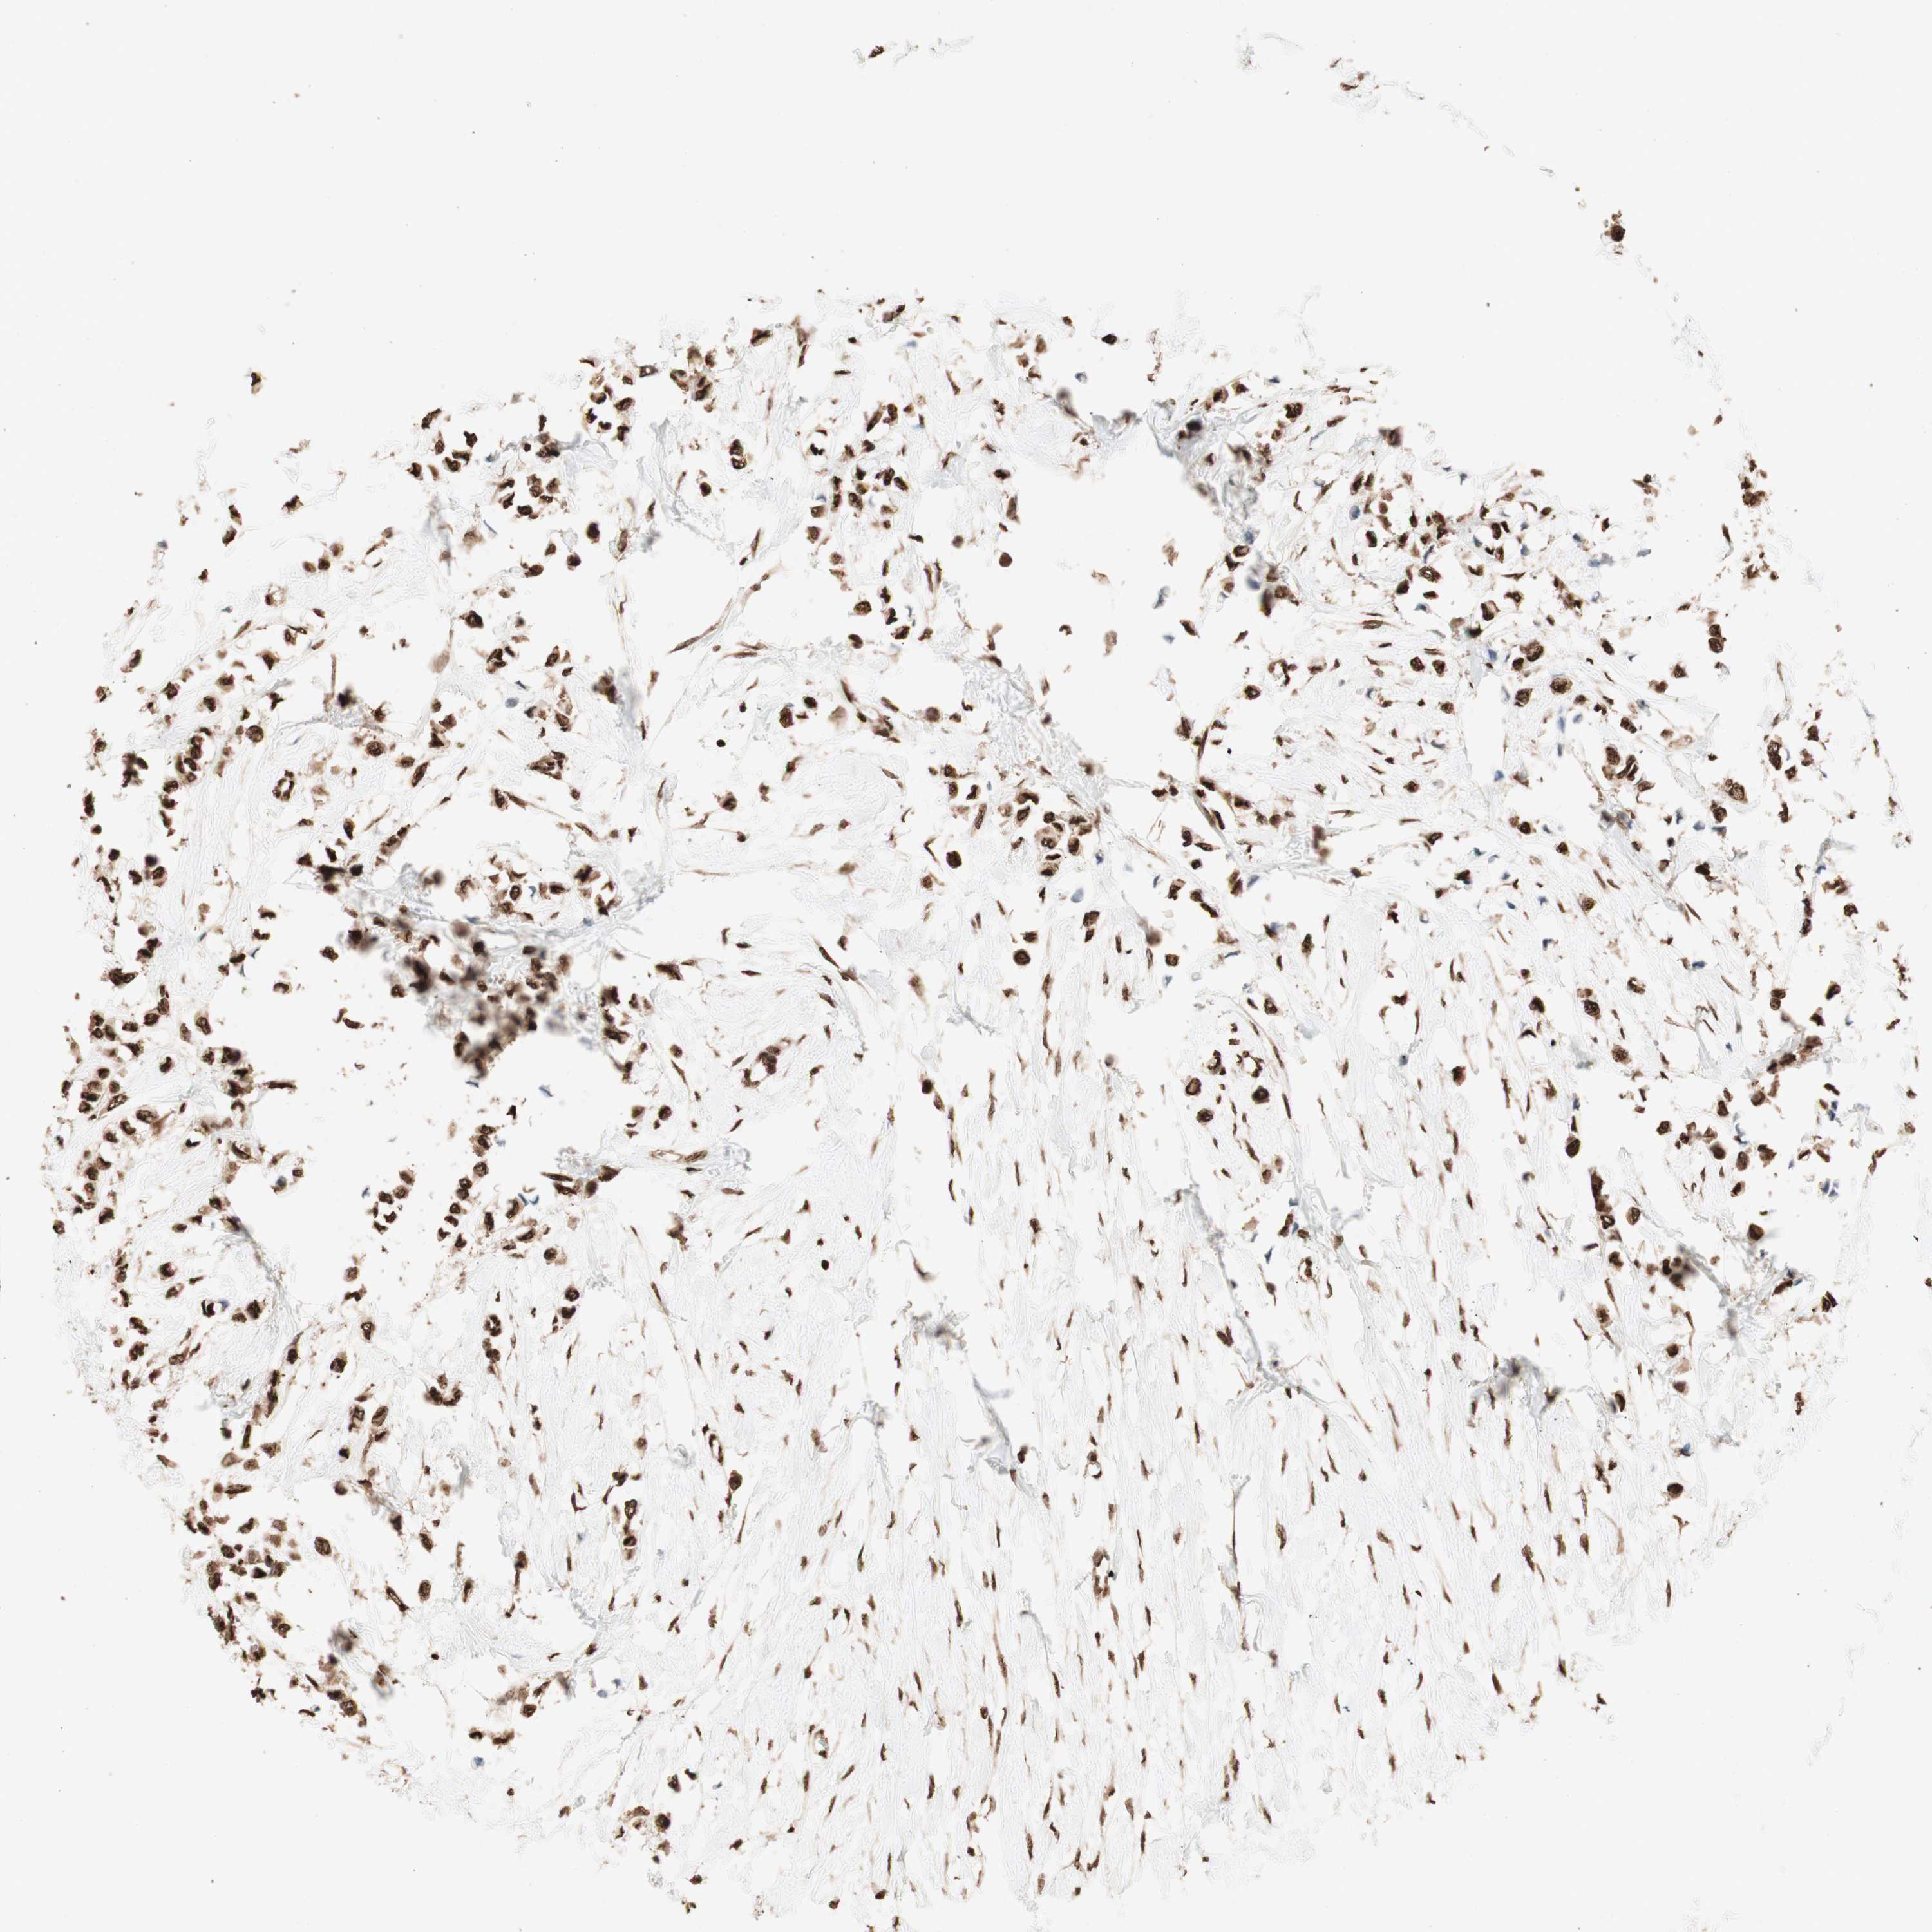

BRCA TCGA BRCA VALIDATION PROTEIN EXPRESSION